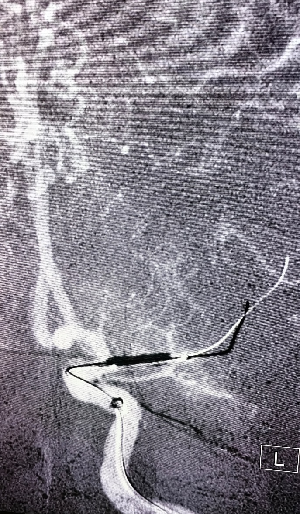

导丝怎么扩【载药时代 球扩天下】NOVA DES®颅内药物洗脱支架在大脑中动脉重度狭窄中的应用两例!_https://www.jmylbn.com_新闻资讯_第7张

导丝怎么扩【载药时代 球扩天下】NOVA DES®颅内药物洗脱支架在大脑中动脉重度狭窄中的应用两例!_https://www.jmylbn.com_新闻资讯_第8张

颈动脉支架释放

在微导丝辅助下将2.25*10mm赛诺神畅颅内药物洗脱支架NOVA DES®于大脑中动脉狭窄处扩张成形术。

导丝怎么扩【载药时代 球扩天下】NOVA DES®颅内药物洗脱支架在大脑中动脉重度狭窄中的应用两例!_https://www.jmylbn.com_新闻资讯_第9张

导丝怎么扩【载药时代 球扩天下】NOVA DES®颅内药物洗脱支架在大脑中动脉重度狭窄中的应用两例!_https://www.jmylbn.com_新闻资讯_第10张

球扩后狭窄解除。